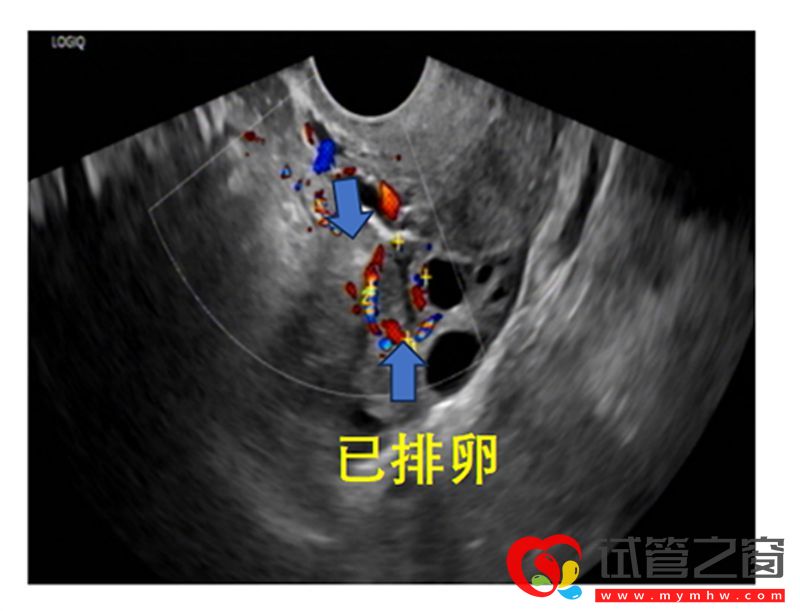

排卵后的变化

成熟卵泡消失或原成熟卵泡直径明显缩小,形态不规则,壁皱缩,卵泡内透声差,可见细弱光点,部分女性会出现子宫直肠凹积液,子宫内膜逐渐由A型转变为C型。